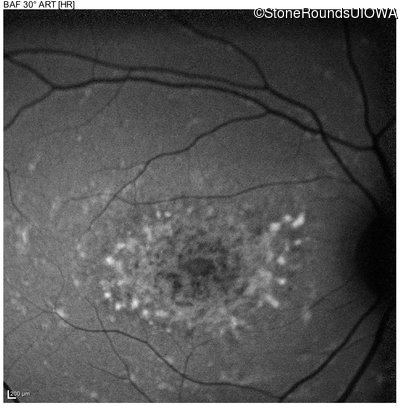

Age at visit: 22 years

Age at visit: 17 years

Age at visit: 18 years

Age at visit: 19 years